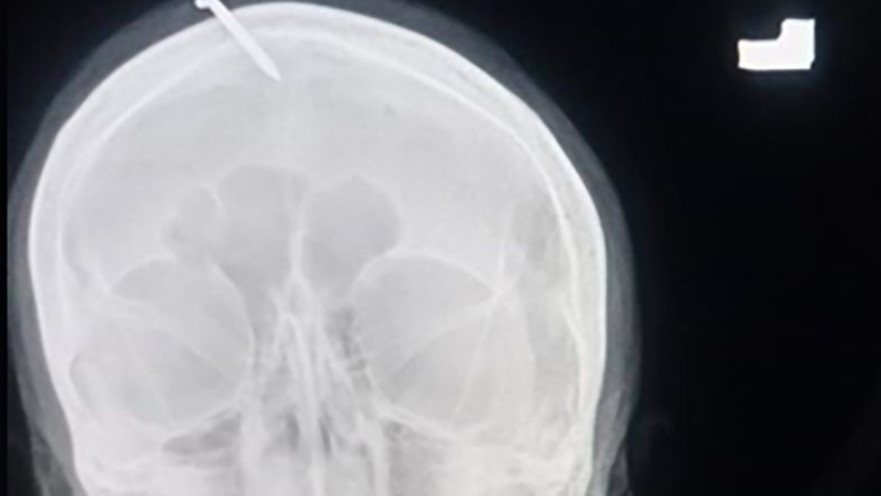

המסמר שהוחדר לראשה של ההריונית

המסמר שהוחדר לראשה של ההריונית | צילום: LADY READING HOSPITAL

על פי הדיווחים, האישה ההריונית פנתה אל מרפא דת שביצע בה הליך רפואי משונה, שלטענתו אמור היה להבטיח שתלד בן. לשם כך, אותו ה"מרפא" החדיר אל ראשה מסמר באורך של כחמישה סנטימטרים שחורר את החלק העליון של מצחה וגרם לה לכאבים בלתי נסבלים.

צילומי הרנטגן של האישה הציגו את המסמר, שפילח את החלק העליון של מצחה אך פספס את מוחה ובכך נמנע נזק בלתי הפיך. ד"ר היידר חאן, שטיפל בה, הסביר כי ככל הנראה השתמשו בפטיש או כל חפץ כבד אחר כדי לדפוק את המסמר פנימה, והוא אף הוסיף כי "היא הייתה בהכרה מלאה וסבלה מכאבים חמורים כשהגיעה אל בית החולים".